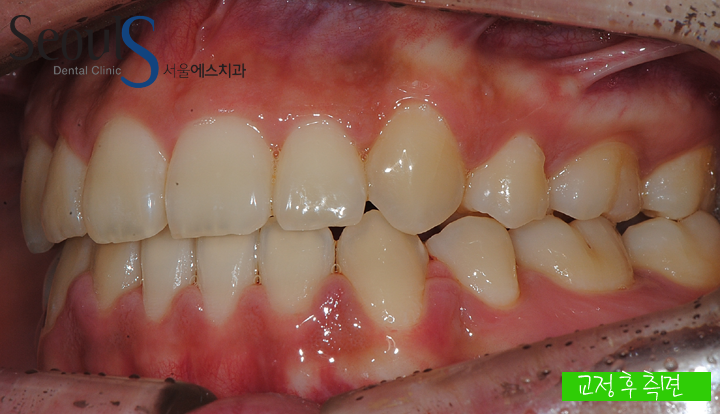

10교정 후 측면 모습입니다

11교정 전후 측면 모습입니다